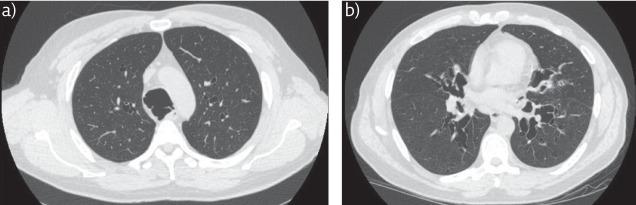

To recognise the clinical and radiological presentation of the spectrum of diseases associated with bronchiectasis.To understand variation in the aetiology, microbiology and burden of bronchiectasis and cystic fibrosis across different global healthcare systems.

Bronchiectasis is the term used to refer to dilatation of the bronchi that is usually permanent and is associated with a clinical syndrome of cough, sputum production and recurrent respiratory infections. It can be caused by a range of inherited and acquired disorders, or may be idiopathic in nature. The most well recognised inherited disorder in Western countries is cystic fibrosis (CF), an autosomal recessive condition that leads to progressive bronchiectasis, bacterial infection and premature mortality. Both bronchiectasis due to CF and bronchiectasis due to other conditions are placing an increasing burden on healthcare systems internationally. Treatments for CF are becoming more effective leading to more adult patients with complex healthcare needs. Bronchiectasis not due to CF is becoming increasingly recognised, particularly in the elderly population. Recognition is important and can lead to identification of the underlying cause, appropriate treatment and improved quality of life. The disease is highly diverse in its presentation, requiring all respiratory physicians to have knowledge of the different "bronchiectasis syndromes". The most common aetiologies and presenting syndromes vary depending on geography, with nontuberculous mycobacterial disease predominating in some parts of North America, post-infectious and idiopathic disease predominating in Western Europe, and post-tuberculosis bronchiectasis dominating in South Asia and Eastern Europe. Ongoing global collaborative studies will greatly advance our understanding of the international impact of bronchiectasis and CF.

认识与支气管扩张相关疾病谱的临床和影像学表现。理解不同全球医疗体系中支气管扩张和囊性纤维化在病因、微生物学及疾病负担方面的差异。

支气管扩张是指支气管扩张,通常为永久性扩张,并伴有咳嗽、咳痰及反复呼吸道感染的临床综合征。它可由一系列遗传性和获得性疾病引起,也可能本质上是特发性的。在西方国家,最广为人知的遗传性疾病是囊性纤维化(CF),这是一种常染色体隐性疾病,可导致进行性支气管扩张、细菌感染和过早死亡。由CF引起的支气管扩张和由其他病症引起的支气管扩张在国际上对医疗体系造成的负担都日益加重。CF的治疗正变得越来越有效,导致更多有复杂医疗需求的成年患者。非CF引起的支气管扩张越来越受到重视,尤其是在老年人群中。识别很重要,可导致找出潜在病因、进行适当治疗并改善生活质量。该疾病的表现形式高度多样,要求所有呼吸内科医生了解不同的“支气管扩张综合征”。最常见的病因和表现综合征因地域而异,非结核分枝杆菌病在北美某些地区占主导,感染后和特发性疾病在西欧占主导,而结核后支气管扩张在南亚和东欧占主导。正在进行的全球合作研究将极大地推进我们对支气管扩张和CF国际影响的理解。